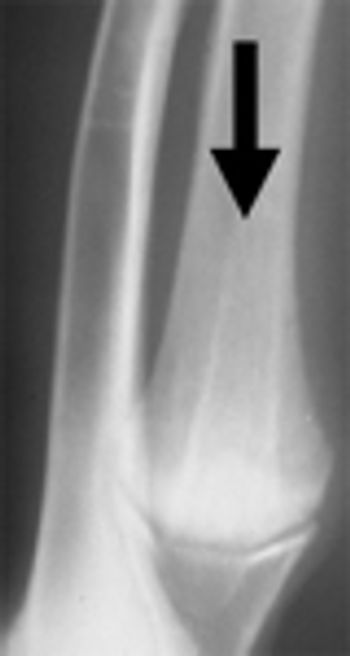

The goal in management of open fractures is to prevent further contamination, prevent additional damage to the bone and surrounding soft tissues especially nerve and vascular supplies and facilitate timely stabilization.

Orthopedic infections should also be thought of as infections involving the bones (osteitis or osteomyelitis), joints and surrounding support structures (periostitis, myelitis, cellulitis). Typically when we think of orthopedic infections we think of infections resulting after orthopedic surgery.